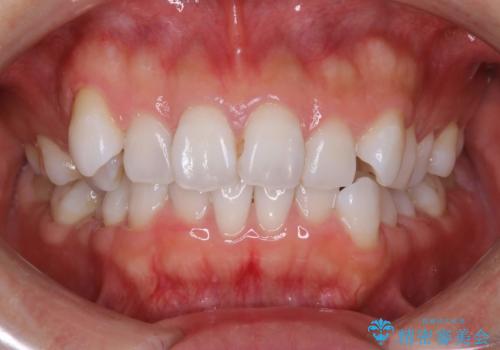

抜歯せずに八重歯のマウスピース矯正

- 30代女性

- invisalign full

- 1年3ヶ月

- 非抜歯・遠心移動+IPR+拡大 によるマウスピース矯正を計画した。

八重歯がシビアな場合、抜歯をしないと治せないケースもありますが、奥歯の位置関係を修正したり、歯のサイズダウンを行うことで、抜歯をせずに改善できる場合もたくさんあります。